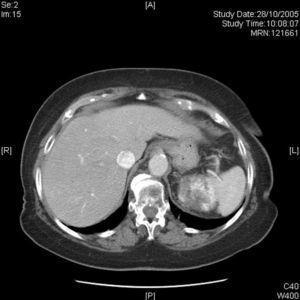

Fig. 2.--TC abdominopélvica con contraste. Masa heterogénea en polo superior del riñón izquierdo.

Una mujer de 76 años, con antecedentes personales de hipertensión arterial y fibrilación auricular crónica, acudió a nuestra consulta remitida desde urgencias por la aparición 5 días antes de lesiones maculosas puntiformes purpúricas en tobillo y dorso de pies, inicialmente asintomáticas. Las lesiones habían ido aumentando en número, extensión y tamaño, afectando a piernas y muslos, con aparición de ampollas hemorrágicas perimaleolares con rotura y formación de costra posterior, acompañándose de prurito. No había fiebre u otra sintomatología asociada. La paciente seguía tratamiento desde hacía años con diltiazem, fosinopril, furosemida, acenocumarol y extracto de ginkgo biloba, y negaba la introducción de medicación nueva previa a la aparición de las lesiones. A la exploración física presentaba, en dorso de pies, piernas y tercio distal de muslos, lesiones papulosas eritematopurpúricas de tamaños variables entre 2 y 5 mm, con lesiones ampollosas hemáticas y costrosas de hasta 10 mm en regiones perimaleolares (fig. 1). Se tomó una biopsia de piel, que mostraba zonas de desprendimiento cutáneo con necrosis epidérmica, y en la dermis leucocitos perivasculares con leucocitoclasia, necrosis fibrinoide de la pared y extravasación hemática; el estudio de inmunofluorescencia directa demostró la presencia de depósito de C3 en los endotelios vasculares de los vasos de la dermis media y superficial. Se ingresó a la paciente para estudio y se instauró tratamiento con 30 mg/día de prednisona oral. Se realizó un estudio analítico completo que incluía sistemático de sangre, bioquímica, sistemático de orina, inmunoglobulinas, complemento, autoanticuerpos, factor reumatoide, crioaglutininas y serología de hepatitis, que mostró como únicos hallazgos discreta leucocituria en orina, anticuerpos anti-VHBc positivos y título de anticuerpos antinucleares (ANA) de 1/160. La radiografía de tórax mostraba cardiomegalia y una imagen nodular en columna dorsal baja, que en la tomografía computarizada (TC) torácica correspondía a una formación exofitaria exuberante de la columna. En esta prueba se visualizaba además una gran masa en la teórica localización del polo superior del riñón izquierdo, por lo que se realizó también una TC abdominopélvica en la cual se observaba una masa heterogénea en dicha localización compatible con un carcinoma renal (fig. 2). Durante el ingreso las lesiones fueron mejorando con prednisona y curas locales, evolucionando a costras. Se realizó una nefrectomía radical laparoscópica por parte del Servicio de Urología, y el estudio anatomopatológico demostró un carcinoma renal de células claras, grado II de Fuhrman, limitado al riñón. Después de la intervención, las lesiones cutáneas han desaparecido completamente sin más tratamiento. Queda pendiente de ver su evolución, dado el escaso tiempo transcurrido desde la cirugía, que es de un mes en la actualidad.